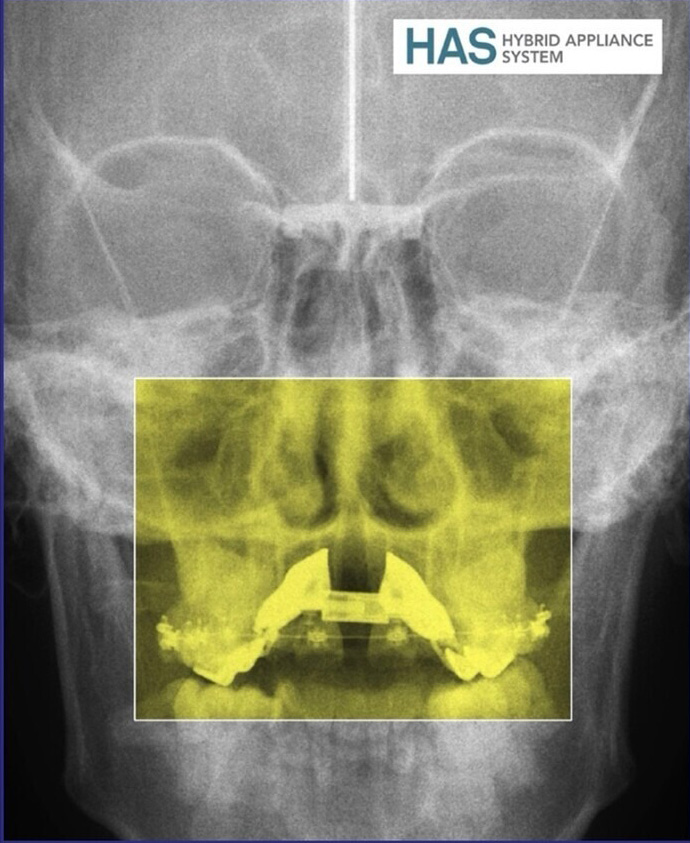

Fieles a nuestros encuentros anuales con la formación continua en Ortodoncia (y, por supuesto, con todos vosotros) la cita de este otoño nos acerca más aún al flujo digital. En esta ocasión nuestro experto invitado es el Dr. Suárez Quintanilla, que nos introducirá en el sistema Hybrid Appliance System y nos abrirá hacia nuevos enfoques.

• 09:00-11:00 “La revolución digital. Protocolos y sistemas expertos en Hybrid Appliance System (HAS)”. Dr. David Suárez Quintanilla